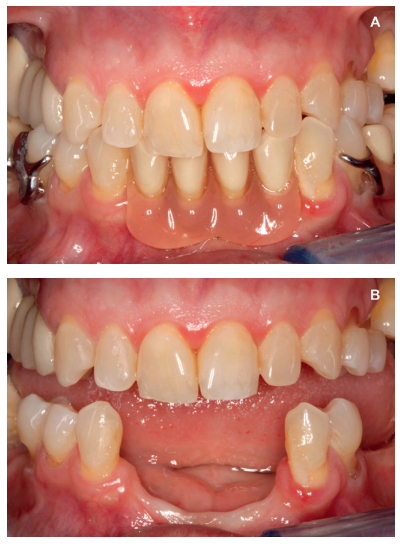

removable prosthesis and (B) the critical defects, especially at the antero-inferior level.